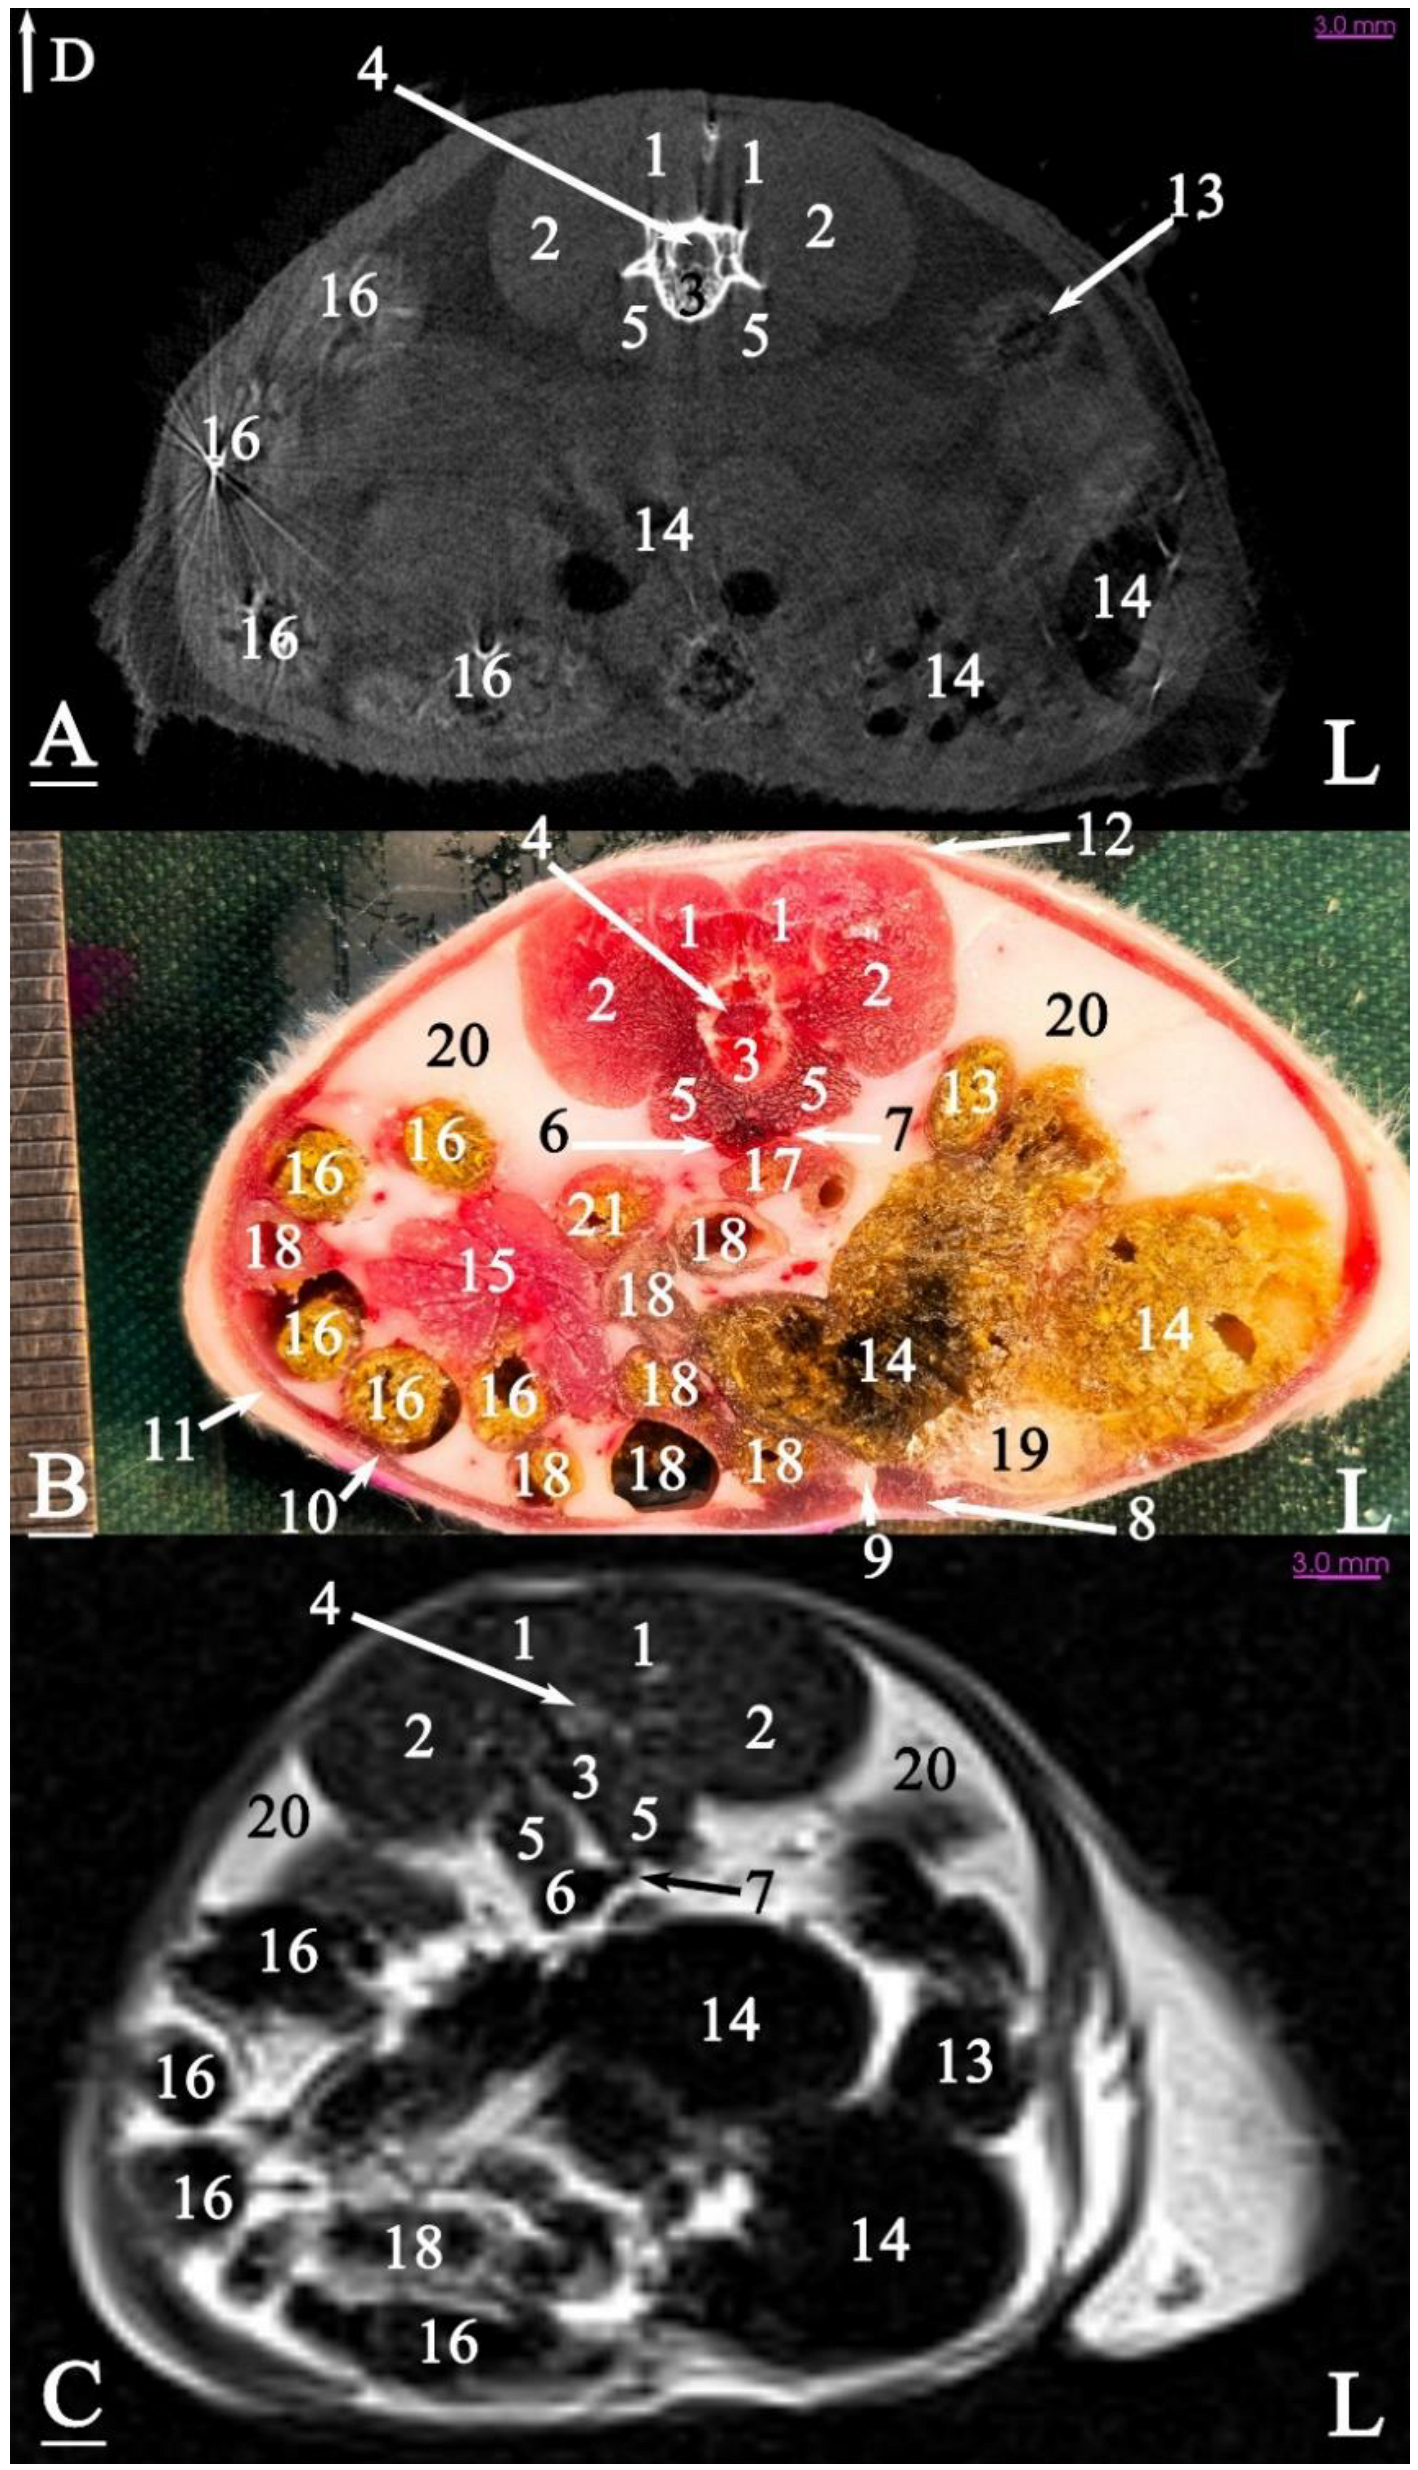

3.2. Anatomical Sectioning

3.2.1. Transverse Cadaver Slices

3.3. Micro-CT Slices

3.4. MRI Slices